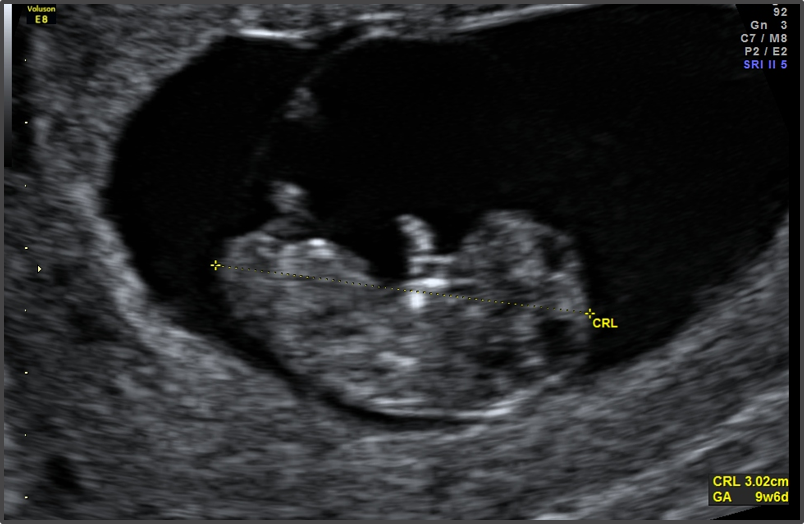

اگر سونوگرافی هفته ۸ را انجام نداده اید, احتمالا سونوگرافی هفته نهم برای محاسبه سن بارداری برای شما برنامه ریزی می شود. اگر از تاریخ آخرین پریود خود مطمئن نیستید, سونوگرافی در این هفته می تواند تاریخ فرضی شما را مشخص کند.

بسته به بارداری هر فرد, پزشک متخصص ممکن است سونوگرافی زودهنگامی را در هفته 9 ام پیشنهاد کند.

اگر این اولین سونوگرافی شما باشد, شانس فهمیدن زمان قطعی زایمان را خواهید داشت مخصوصا اگر از تاریخ آخرین پریود خود مطمئن نباشید.

سونوگرافی در هفته 9 می تواند از طریق واژن یا به صورت خارجی بر روی شکم انجام گیرد.

در سونوگرافی هفته نهم چه چیزهایی دیده می شود؟

در هفته نه شما قادر به دیدن سر, بدن و دست و پای فرزند خود هستید و ممکن است برای اولین بار قادر به شنیدن ضربان قلب رویان خود با مانیتور داپلور هستید. ممکن است لحظه ای بسیار احساسی برای شما باشد پس بهتر است به همراه خود دستمال کاغذی ببرید.

ویژگی های رویان در هفته نه

اندازه رویان در هفته نهم تقریبا 2.5 سانتی متر است.

رویان شبیه زیتون سبزی است که کمتر از 2 گرم وزن دارد

چشمان رویان رشد کرده و بزرگ تر شده و حتی رنگ هم دارد اما چشمهایش توسط پلک ها بسته هستند.

در این هفته همچنین می توانید ابتدای تشکیل انگشتان دست و پا را ببینید.